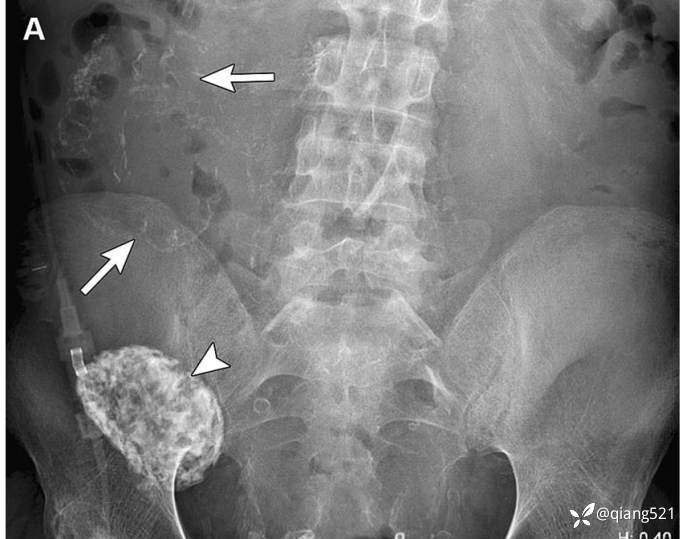

一名 60 岁男子,因长期腹膜透析而患上硬化性腹膜炎。A 腹部 X 光片显示右上腹有弧形钙化(箭头),NECT(B)检查证实内脏腹膜有钙化。同时注意到右下腹肾移植(A)的钙化(箭头所示)